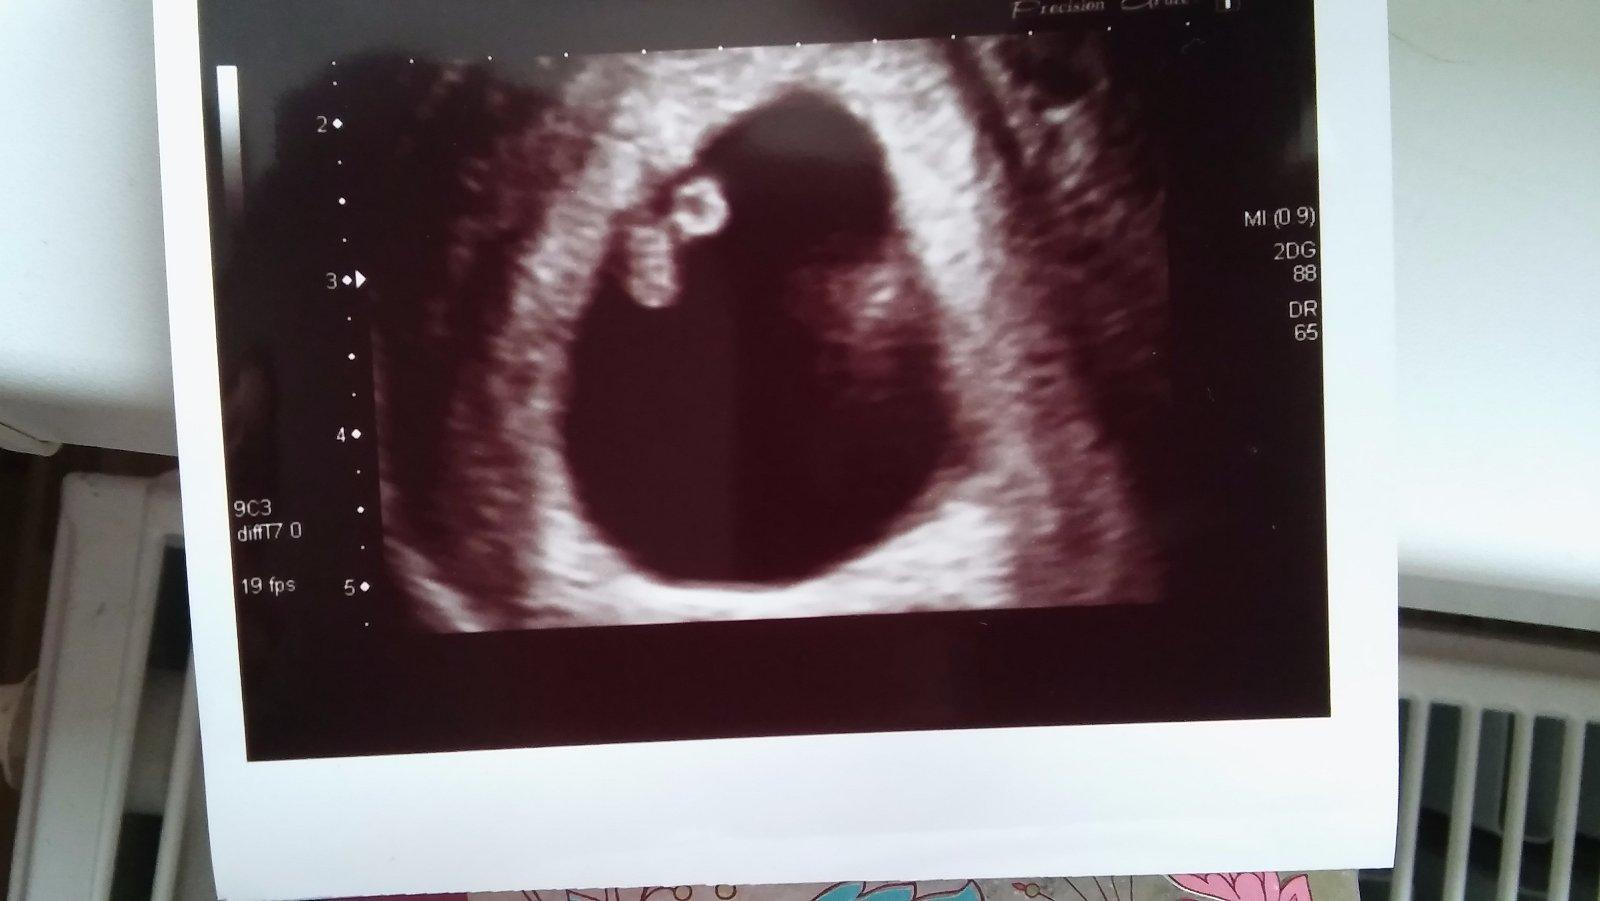

tak dneska jsme byli s malickym na prvnim foceni 🙂 srdicko nam bije o 106 ❤ pan doktor z nas ale nemel radost kdyz se dozvedel,ze jsem znova tehotna. Zjistil,ze jsem byla na kontrole 25.10. kde mi doporucil 2-3 mesice pockat nez se budeme znova snazit. jenze moje PM byla 30.10. 😀 tak jsme se pak i zasmali,protoze rikam ze to neni mozny,ze si urcite spletl datum. Ale malicky je v poradku a doktor rikal,ze to vypada lepe nez to moje prvni tehu.

@lokinsoon To je něco tak překrásnýho 😀 úplně se tu rozplývám.. Hlavně ať je ti dobře a jste oba zdraví!!! 😘

@lokinsoon No vidíš, jak je kuliferda šikovný🙂😍

Moc ti držím palce ať jde všechno jak má. Hlavně buď v klidu, teď když víš že je malý v pořádku, tak se zbytečně nestresuj🙂

Moc se opatruj a snad ten tvůj prďola nebude pořádat moc velké mejdany tam uvnitř, ať pak moc nezvracíš a nemáš kocovinu 😀